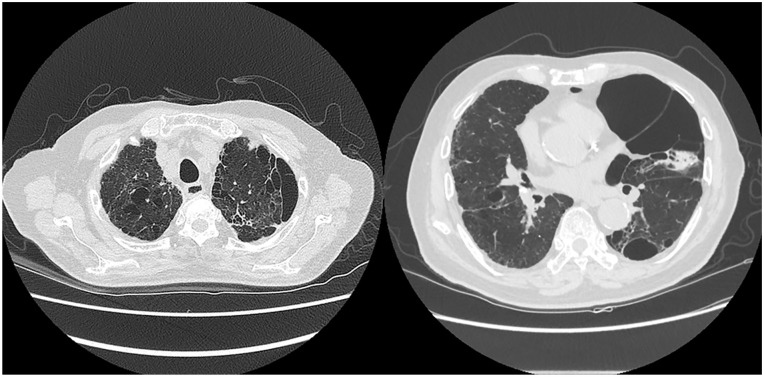

我报告2例老年继发性自发性气胸患者用50%葡萄糖水(DW)进行胸膜融合术。在这两个病例中,胸部计算机断层扫描显示大气胸伴肺气肿和多个大泡。考虑到患者的年龄和潜在的肺部疾病,预计他们不会忍受手术治疗。以前,胸膜固定术是使用其他化学药剂进行的。然而,化学性胸膜穿透术可伴有胸痛、发热,很少伴有呼吸衰竭。2例胸膜截留术,胸膜截留率50%,气胸消退,无并发症。我建议即使是不能耐受手术或化学胸膜固定术的老年患者,也可以考虑使用50% DW胸膜固定术,因为它相对更安全有效。

I report 2 cases of pleurodesis with 50% dextrose water (DW) in very elderly patients with secondary spontaneous pneumothorax. In both cases, a chest computed tomography scan showed a large pneumothorax with emphysema and multiple bullae. Patients were expected not to tolerate surgical treatment, considering their old age and underlying pulmonary disease. Previously, pleurodesis is performed using other chemical agents. However, chemical pleurodesis can be associated with chest pain, fever, and rarely, respiratory failure. Pleurodesis with 50% DW was performed in 2 patients with resolution of pneumothorax without complications. I recommend that even in elderly patients who could not tolerate surgery or chemical pleurodesis, pleurodesis using 50% DW could be considered because it is relatively safer and effective.